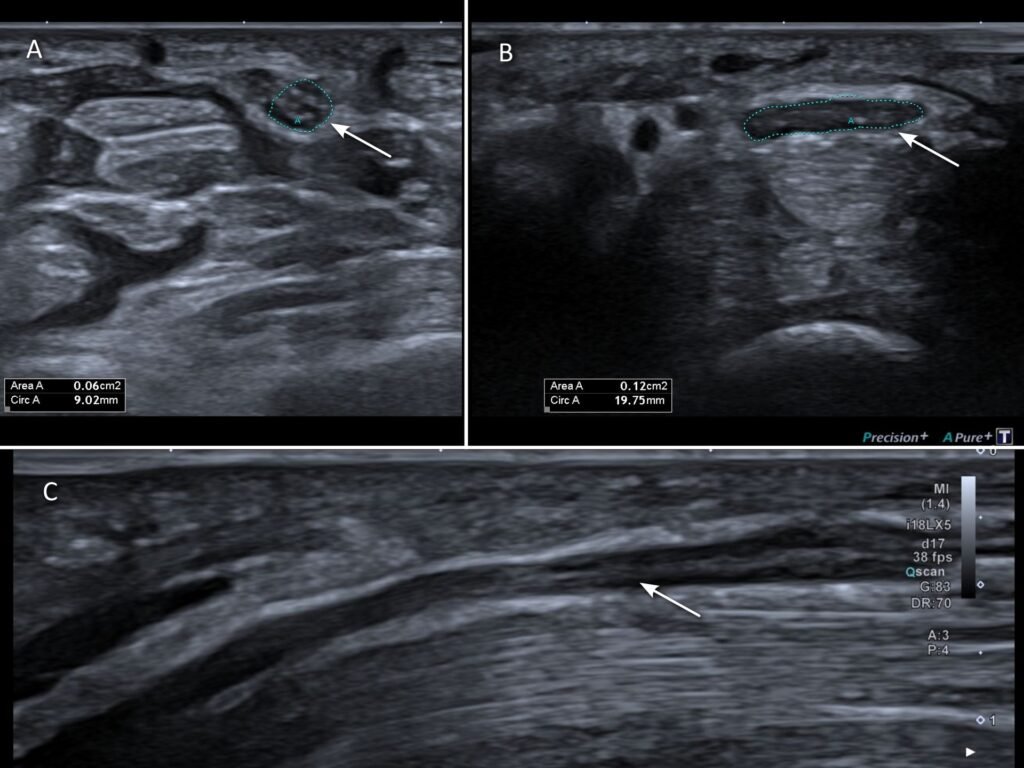

Changes of the median nerve seen on ultrasound very accurately predict carpal tunnel syndrome. Multiple parameters are considered when evaluating for carpal tunnel syndrome, such as thickening and flattening of the nerve [4] (Figure 7), as well as swelling of the overall carpal tunnel content.